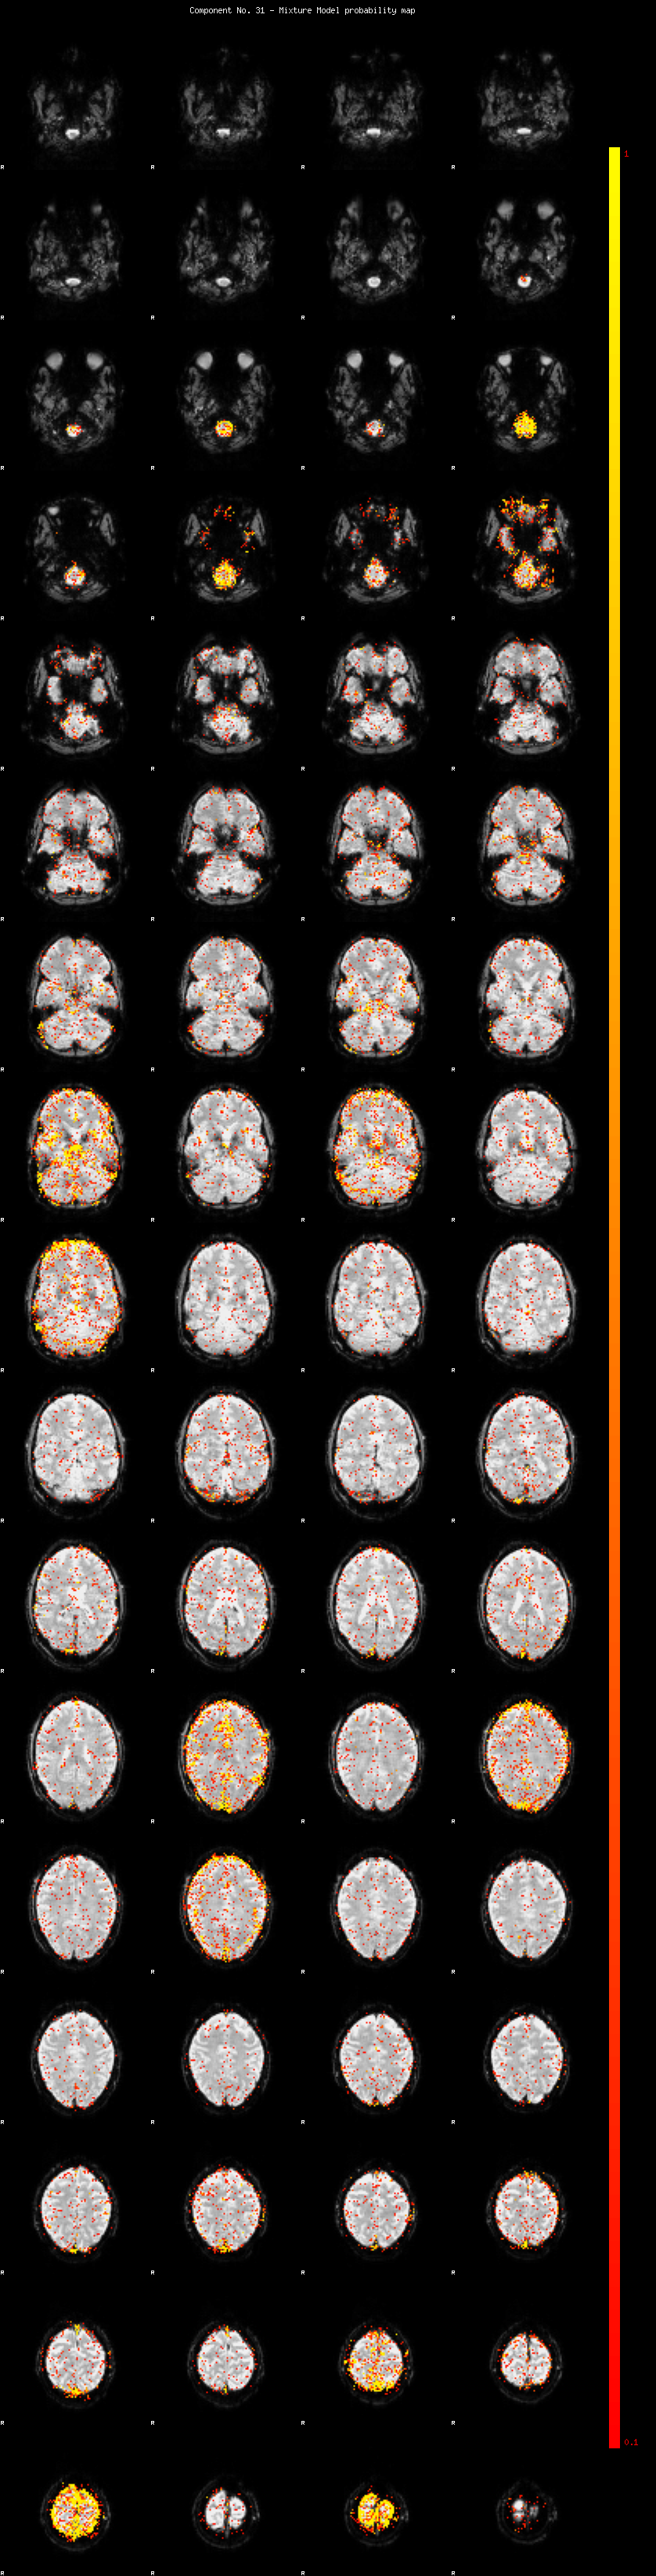

IC_31 Mixture Model fit

Means : -0.000000 3.097452 -2.768098

Vars : 1.000000 4.419120 3.089353

Prop. : 0.939862 0.031676 0.028462